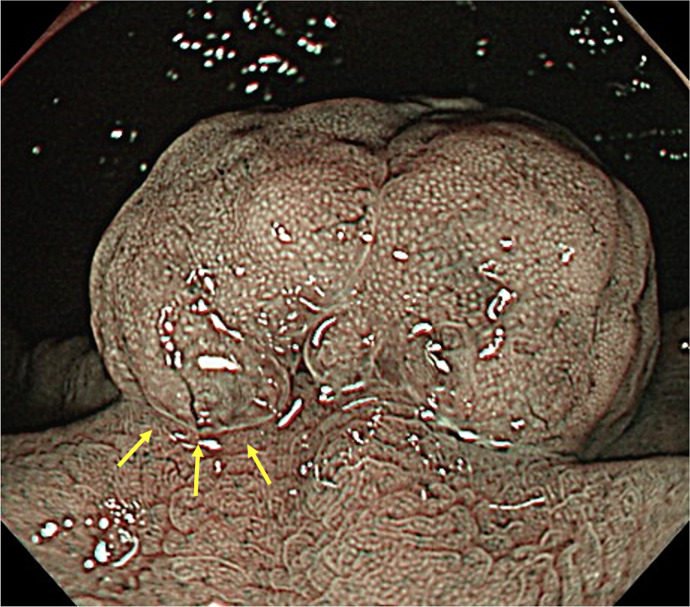

Case presentation: A female patient in her 60s had been taking PPI for reflux esophagitis for >10 years. An upper gastrointestinal endoscopy revealed two gastric polyps measuring 20 mm and 10 mm. She was referred to our hospital for resection, but narrow-band imaging revealed a nonneoplastic lesion. PPI was discontinued, and step-down therapy using vonoprazan was performed. During the treatment, a lifestyle guidance app (Muneyake PRO) was used to record daily heartburn symptoms, oral medication status, and daily life status. She was worried that her symptoms would worsen due to discontinuation, but she gained her understanding when the use of the app to monitor her symptoms was explained. The app was useful for understanding the progress of symptoms and the status of oral medication. Step-down therapy was performed only twice after PPI discontinuation, symptoms have not worsened, and follow-up endoscopy revealed significant gastric polyp shrinkage.